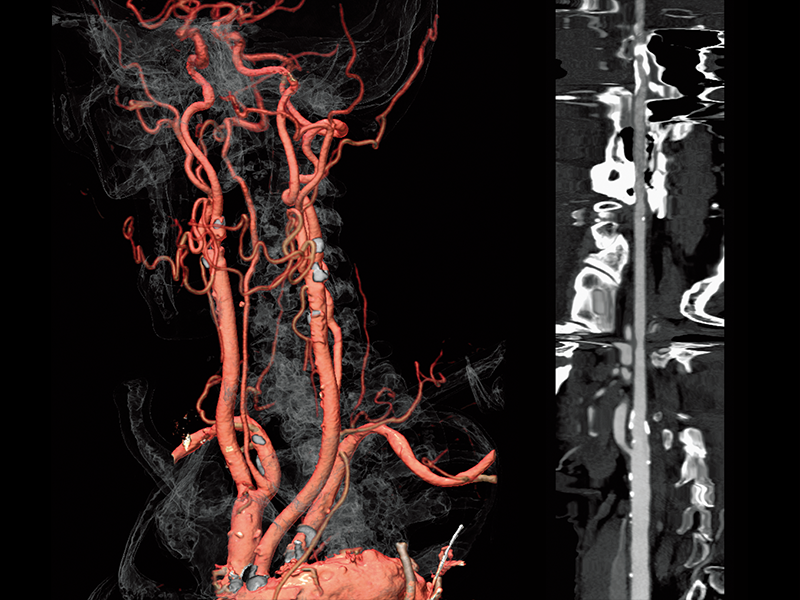

Common carotid artery stenosis

Abdominal aortic occlusion

Left common iliac artery occlusion(Right)